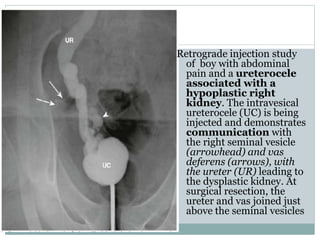

Retrograde injection study

of boy with abdominal

pain and a ureterocele

associated with a

hypoplastic right

kidney. The intravesical

ureterocele (UC) is being

injected and demonstrates

communication with

the right seminal vesicle

(arrowhead) and vas

deferens (arrows), with

the ureter (UR) leading to

the dysplastic kidney. At

surgical resection, the

ureter and vas joined just

above the seminal vesicles